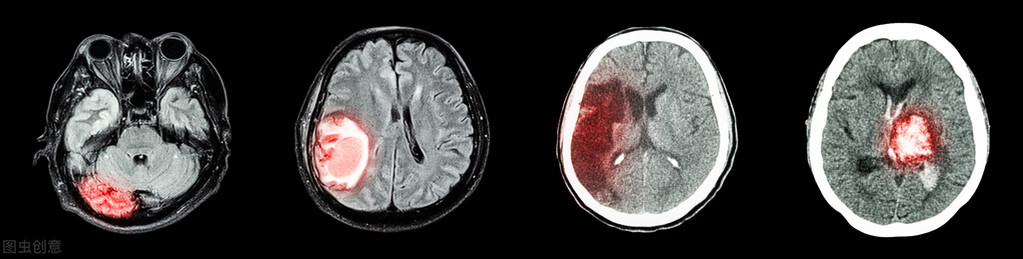

一个大脑要么出血要么梗,到底要怎么治疗?

发生在常人身上最常见的两大脑病,一是脑出血二就是脑梗,一个出来了,一个不通了,其实在治疗的原则上有几个大方向是一致的。